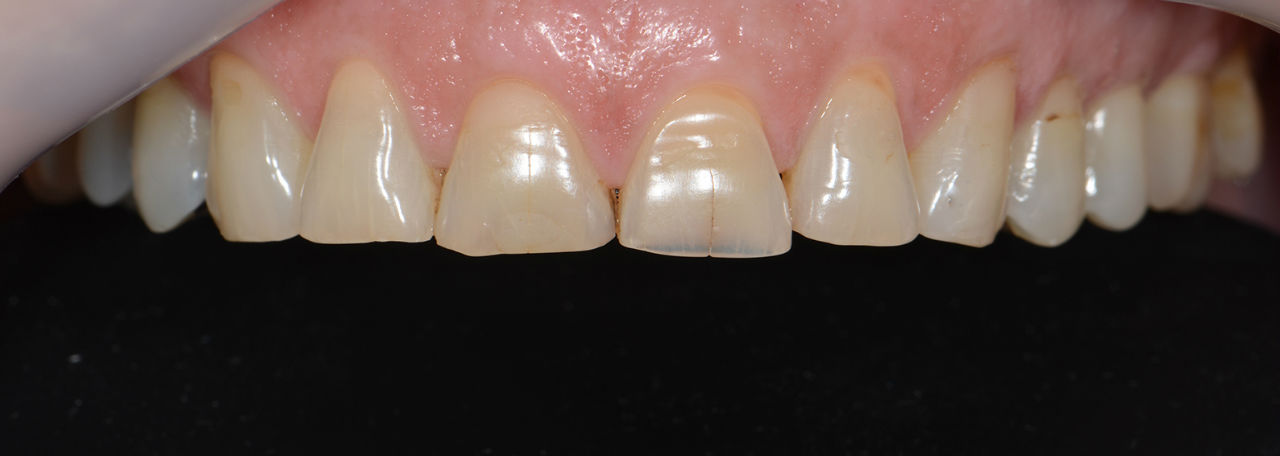

Случай 1: Дигитален дизайн на усмивката в Дента Консулт

Лечение без импланти